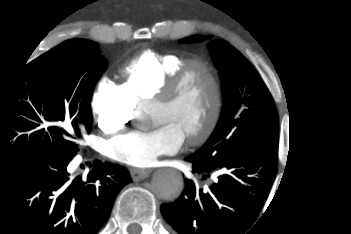

Компьютерная томография сердца является высокотехнологичным лучевым методом исследования, который позволяет оценить строение и особенности анатомии камер сердца, визуализировать состояние перикарда, коронарных артерий и восходящей части и дуги аорты.

В нашей клинике КТ сердца проводится на новейшем 128-срезовом мультиспиральном компьютерном томографе экспертного уровня TOSHIBA AQUILION CXL. Томограф послойно сканирует анатомическую область сердца, производя срезы толщиной от 0,5 мм. Методика сканирования сердца 128-срезовым КТ сканером производится с использованием перспективной синхронизации по электрокардиографии (ЭКГ).

Протокол сканирования предусматривает внутривенное болюсное контрастирование. Контрастное вещество на основе йода вводится пациенту внутривенно непосредственно во время исследования. Контраст равномерно распределяется по сосудистой системе, благодаря чему становится хорошо видна восходящая часть аорты с отходящими от нее венечными артериями и дуга аорты. По результатам обследования можно решить, нуждается пациент в проведении стентирования коронарных артерий или нет.